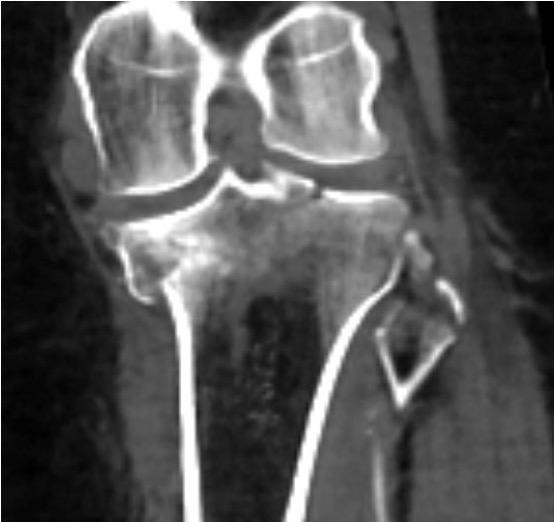

CT demonstrating medial tibial plateau in setting of knee dislocation and posterolateral corner injury